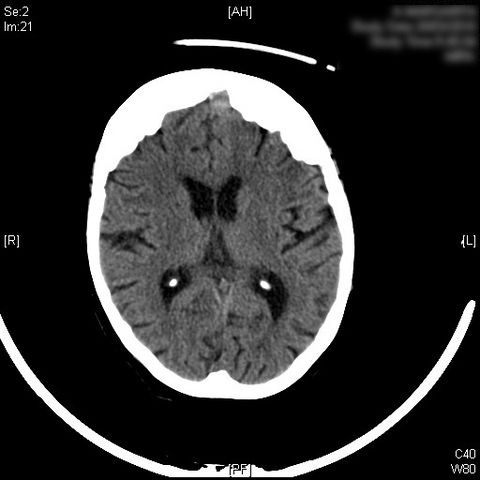

Higroma frontal bilateral

AVC amplio de territorio de A. cerebral media

Hematoma subdural por caída.

Atrofia cortico-subcortical de predominio frontotemporal.